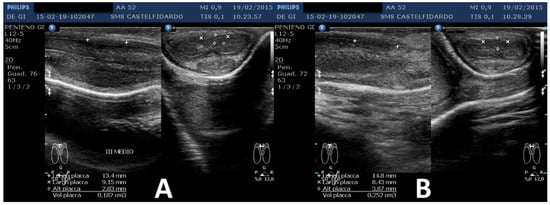

| 2 | 52 years | Dupuytren’s disease, Ledderhose disease, congenital dorsal penile curvature (5 degrees). | Middle third + distal third | (A) First plaque: 13.4 × 9.15 × 2.83 mm volume = 182 mm3. Second plaque: 14.8 × 8.43 × 3.87 mm. Total volume = 252 mm3 (B) No plaque detected | (A) 20-degree dorsal penile curvature + 20-degree left penile curvature (B) 5-degree dorsal penile curvature. Previous condition = congenital dorsal penile curvature (5 degrees) | VAS score = 0 | 26 > 27 | 51 months | Orally: propolis 600 mg + bilberry 160 mg + silymarin 400 mg + ginkgo biloba 250 mg + L-carnitine 1000 mg + coenzyme Q10 100 mg + Boswellia 200 mg + vitamin E 30 mg/daily for 51 months + topically: diclofenac gel 4%/2× daily for 51 months + periplaque penile injections: pentoxifylline 100 mg (30 G needle) every 2 weeks for 6 months, and then 1 penile injection every month for 12 months, and 1 penile injection every 2 months for 24 months (42 total injections) |